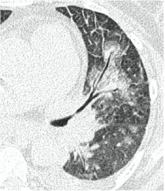

2. Наличие клинических проявлений, указанных в п. 1, в сочетании с характерными изменениями в легких по данным компьютерной томографии (КТ) (см. Приложение 1 настоящих рекомендаций) вне зависимости от результатов однократного лабораторного исследования на наличие РНК SARS-CoV-2 и эпидемиологического анамнеза.

- Изменения при КТ (рентгенографии), типичные для вирусного поражения (объем поражения минимальный или средний; КТ 1 - 2)

- Изменения в легких при КТ (рентгенографии), типичные для вирусного поражения (объем поражения значительный или субтотальный; КТ 3 - 4)

- Изменения в легких при КТ (рентгенографии), типичные для вирусного поражения критической степени (объем поражения значительный или субтотальный; КТ 4) или картина ОРДС.

КТ имеет высокую чувствительность в выявлении изменений в легких, характерных для COVID-19. Применение КТ целесообразно для первичной оценки состояния ОГК у пациентов с тяжелыми прогрессирующими формами заболевания, а также для дифференциальной диагностики выявленных изменений и оценки динамики процесса. КТ позволяет выявить характерные изменения в легких у пациентов с COVID-19 еще до появления положительных лабораторных тестов на инфекцию с помощью МАНК. В то же время, КТ выявляет изменения легких у значительного числа пациентов с бессимптомной и легкой формами заболевания, которым не требуется госпитализация. Результаты КТ в этих случаях не влияют на тактику лечения и прогноз заболевания при наличии лабораторного подтверждения COVID-19. Поэтому массовое применение КТ для скрининга асимптомных и легких форм болезни не рекомендуется.